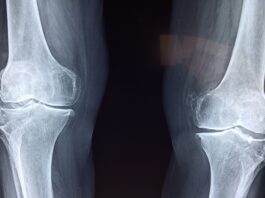

Artrosi del ginocchio: la fisioterapia digitale migliora dolore e funzione

Le tecnologie digitali stanno assumendo un ruolo crescente nella riabilitazione dei pazienti con patologie muscoloscheletriche. Una nuova revisione...